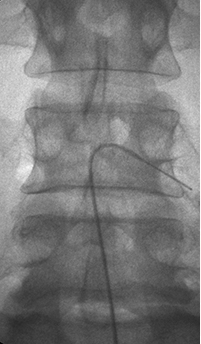

좁아진 신경 통로에 풍선 카테터를 넣어 공간을 넓히고 약물을 주입해,

다리 통증과 저림을 줄이는 최소침습 척추 시술입니다.

가느다란 카테터를 경막외 공간에 넣어 목(경추)·허리(요추) 신경 주변 유착과 염증을 풀어주고,

통증을 완화하는 최소침습 척추 시술입니다.